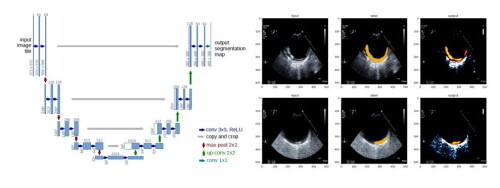

연구팀은 머신러닝의 다양한 기법 중 오토엔코더(Autoencoder)와 유넷(U-net)모델을 대동맥벽의 초음파 영상 판별에 적용했다. 대동맥벽을 초음파 영상으로 판별하면 뇌졸중의 원인으로 떠오르고 있는 대동맥 동맥경화성 플라크의 상태를 확인할 수 있다.

| ▲ 유넷모델을 이용한 플라크 영역 예측 사례 (사진= 한국기계연구원 제공) |